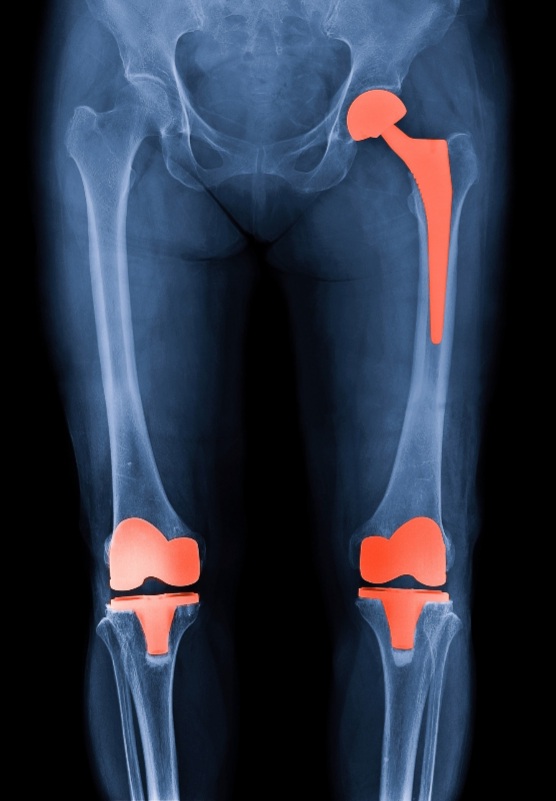

- Πλήρεις ή μερικές αντικαταστάσεις άρθρωσης γόνατος (αρθροπλαστική)

- Ολικές αντικαταστάσει άρθρωσης ισχίου (αρθροπλαστική)